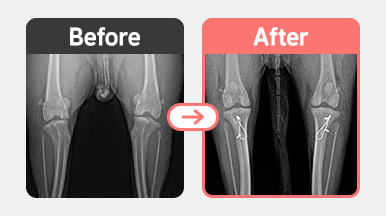

진단명 : 양측 슬개골 탈구 / 우측 G2 좌측 G3

우측 2기 : 대퇴고랑성형 + 경골조면 이식

좌측 3기 : 대퇴고랑성형 + 경골조면 이식 + 외측관절낭 부분절제

우측은 무릎 홈이 얕아 슬개골이 쉽게 빠지는 상태로, 대퇴고랑성형(trochleoplasty) 과 경골조면 이식(TTT)을 통해 정렬을 교정하였습니다.

좌측은 탈구가 더 심하고 관절낭 긴장도가 낮아져 있어

홈 성형 + TTT에 더해 외측관절낭 부분절제까지 시행하여 안정성을 강화했습니다.

수술 후 양측 슬개골 정복 상태는 안정적으로 유지되고 있으며,